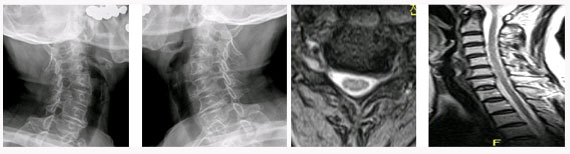

척추관 협착증의 방사선 소견